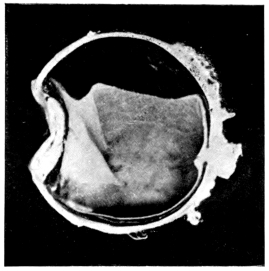

PLATE III.

16.

ABUNDANT EXUDATE INTO VITREOUS CAVITY

curly bracket span

17.

LENS FIRMLY FIXED BY ORGANIZED EXUDATE

18.

LENS FIRMLY FIXED BY ORGANIZED EXUDATE, BUT IN UNUSUAL POSITION

19.

TOTAL DETACHMENT OF RETINA, WITH CYST FORMATION

20.

RECLINED LENS LYING IN FRONT OF THE HYALOID BODY

21.

RECLINED LENS LYING IN FRONT OF THE HYALOID BODYxii